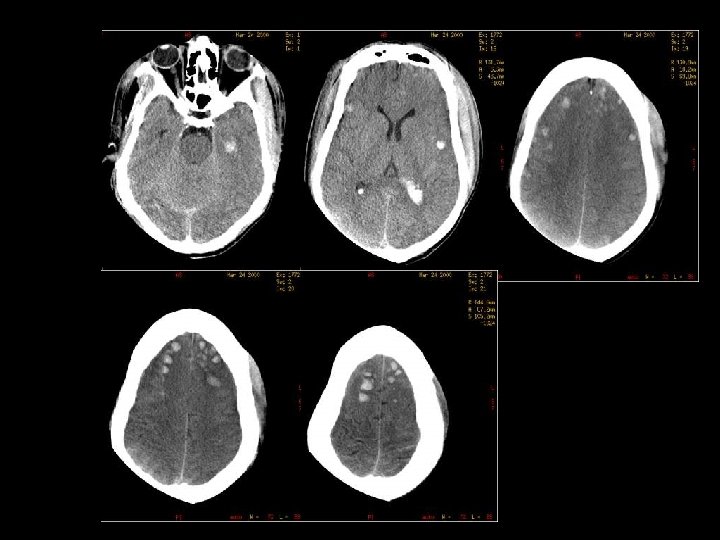

SUBDURAL HEMATOMA n Timbul antara dura dan arachnoid n Dapat melewati sutura n Timbul akibat disrupsi bridging cortical veins n Bentuk konkaf n Hipodens(hiperakut, kronis), isodens(subakut), hiperdens(akut)

W=33 L=41

EPIDURAL HEMATOMA n Berlokasi antara skull dan periosteum n Akibat laserasi arteri meningea media atau vena dural n Dibatasi oleh sutura n Bentuk lentiform / bikonveks